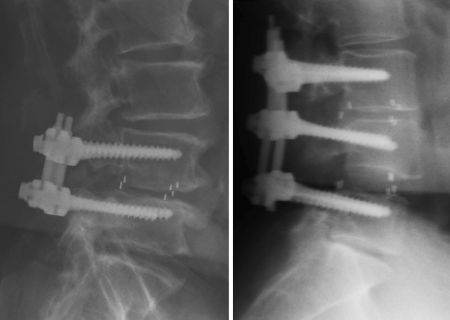

Despite the fact that none of the patients in this study was clinically symptomatic, evidence of vertebral endplate osteoclastic activity was demonstrated radiographically in all 17 patients in 3 months following surgical intervention (Fig. 2). Radiographic evidence of fusion was apparent in all patients at 6 months (Fig. 3). Ossification of the decalcified areas of the vertebrae was evident in all patients at the 6-month assessment and seen at all subsequent examinations.

Fig. 2.

Radiographical assessment of the 3-month patients; to demonstrate the resorption at the perimeter of the cage and osteclastic activity